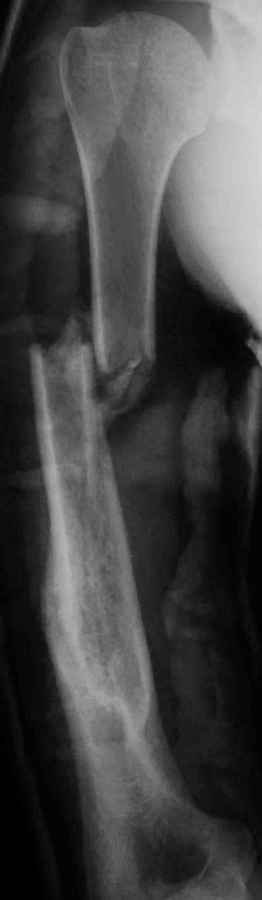

Несмотря на то, что всё это "хорошо компенсируется функционально" В приложенном файле - случай ложного сустава плеча, сформировавшегося после консервативного лечения перелома.(И почему эти оставшиеся 10% так часто попадают ко мне!). Пациент 51 года, соматически здоровый некурящий житель московских окраин ("спальный" район), 4 года назад лечился в одной из наших клинических больниц. Его заверили в том, что переломы плеча срастаются всегда, а уж если у него нет консолидации, то оперировать тем паче нельзя ввиду жуткой биологии. И только на 5ом году болезни он решил узнать второе мнение. Я не был оригинален - аутоспонгиоза, хронос плюс блокированная пластина (см вложенный файл). Ещё раз подчеркну, что я не отрицаю других путей в лечении этого ложного сустава. Но я выбрал данный. Удачи. Киев - Москва. Андрей Волна

Кликните для загрузки файла Лс плеча после консервативного лечения(1).pdf